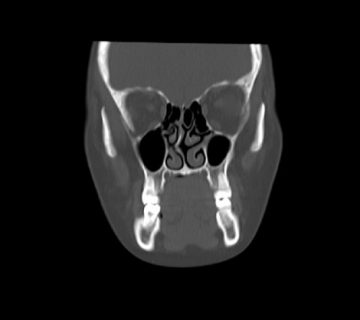

La punta se considera la porción más distante de la nariz, desde las mejillas. Esta debe tener ciertos ángulos específicos y proporciones determinadas dependiendo del rostro de cada paciente.

Lo ideal es que la punta nasal del rostro femenino tenga un ángulo nasolabial entre 100º y 110º grados, así mismo, en el rostro masculino entre 90º y 100º. Si el ángulo es menor, estaremos ante una punta nasal caída, que podría dar lugar a dificultades respiratorias.

De igual manera, cuando la punta tiene un ángulo mayor al especificado, el rostro presenta un aspecto asincrónico que dará el resultado conocido como «punta respingada».